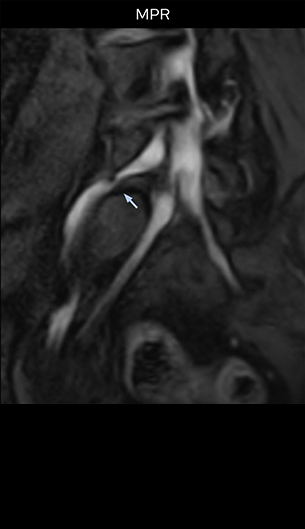

“For example, in sagittal images, when the presence of fat is observed in the intervertebral foramen, it suggests that there is a margin around the nerve. Similarly, the absence of fat indicates that the nerve is being compressed. So, we used to deduce nerve compression indirectly. With NerveVIEW, however, we can observe the condition of the nerves directly, regardless of the presence or absence of fat. We always prefer such direct observation of anatomy over having to make an inference about it.”

Distinguishing typical from atypical herniation informs the surgeon

“NerveVIEW is really useful for those cases where a nerve disorder is strongly suspected based on the clinical examination but our regular MRI images do not show any findings. These atypical herniations and spinal canal stenosis, occurring in 5% to 15% of the total lumbar herniation/stenosis cases are our main target when using NerveVIEW,” says Dr. Yabuki.

“Although symptoms of typical disc herniation and atypical hernia are very similar, the actual site of herniation is different. It is therefore important to characterize the nerve’s condition both inside and outside of the intervertebral foramina.

“Recently, the two surgical methods extreme and oblique lateral interbody fusion (XLIF and OLIF) have become mainstream for minimally invasive treatment of lumbar spinal canal stenosis and intervertebral foramen stenosis. With these surgical techniques, the spine is approached from the flank, and prior knowledge of the exact anatomy of the lumbosacral plexus would be extremely helpful. To that end, high slice resolution (less than 1 mm acquisition) that enables sharper sagittal MPR images will be needed.”